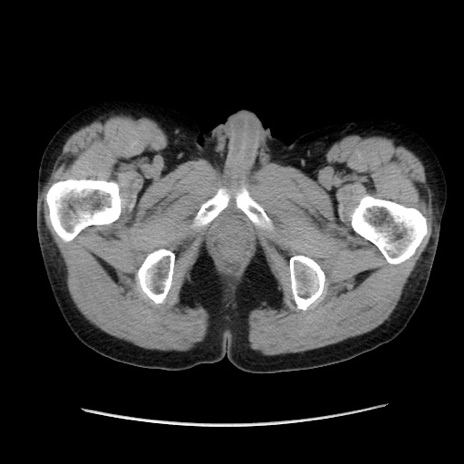

冠状断像

【症例】40歳代 男性

【主訴】腹痛

【現病歴】4時間ほど前に電車に乗車中に臍部上より腹痛出現。徐々に増悪し起立困難となり、救急外来受診。生ものは数日食べていない。今朝お雑煮を食べた。

【身体所見】BT 36.8℃、BP 117/84mmHg、HR 91/min、SpO2 97%、苦悶様、腹部:臍上部広範囲圧痛あり、反跳痛±

【データ】WBC 8100、CRP 0.03